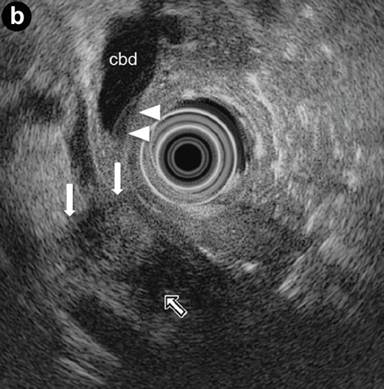

A 21-year-old woman presented with abdominal pain and a sonographic finding of a dilated main pancreatic duct in both the body and the tail sections. Axial images of the contrast-enhanced CT scan (arterial phase) (Image 4a) showed an enlarged pancreatic head with a hypodense lesion (arrow). Radial scanning EUS (Image 4b) confirmed a hypoechoic focal lesion of the pancreatic head (arrows) with an upstream dilatation of the common bile duct; the choledochal wall showed thickening with a "sandwich-pattern" (arrowheads). IgG4 levels were elevated.

|

Image 4 |